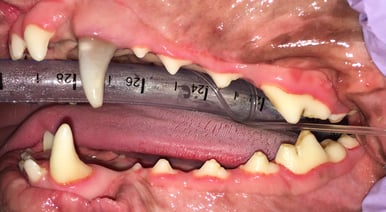

A root canal procedure was performed on tooth 204, which was non-vital. To access the pulp chamber, a round surgical length bur was utilized. Upon reaching the pulp chamber, a radiograph was taken to ensure cleaning at the working length, which in this case was 38mm. Cleaning and shaping of the canal were carried out using Dentsply NiTi and LightSpeed files in alternation with suction aided sterile saline and sodium hypochlorite solutions.

Below: During RCT - Radiograph finding working length to clean and measure canal

%20-%20March%202024/during%20RCT%20-%20finding%20working%20length.jpg?width=379&height=291&name=during%20RCT%20-%20finding%20working%20length.jpg)